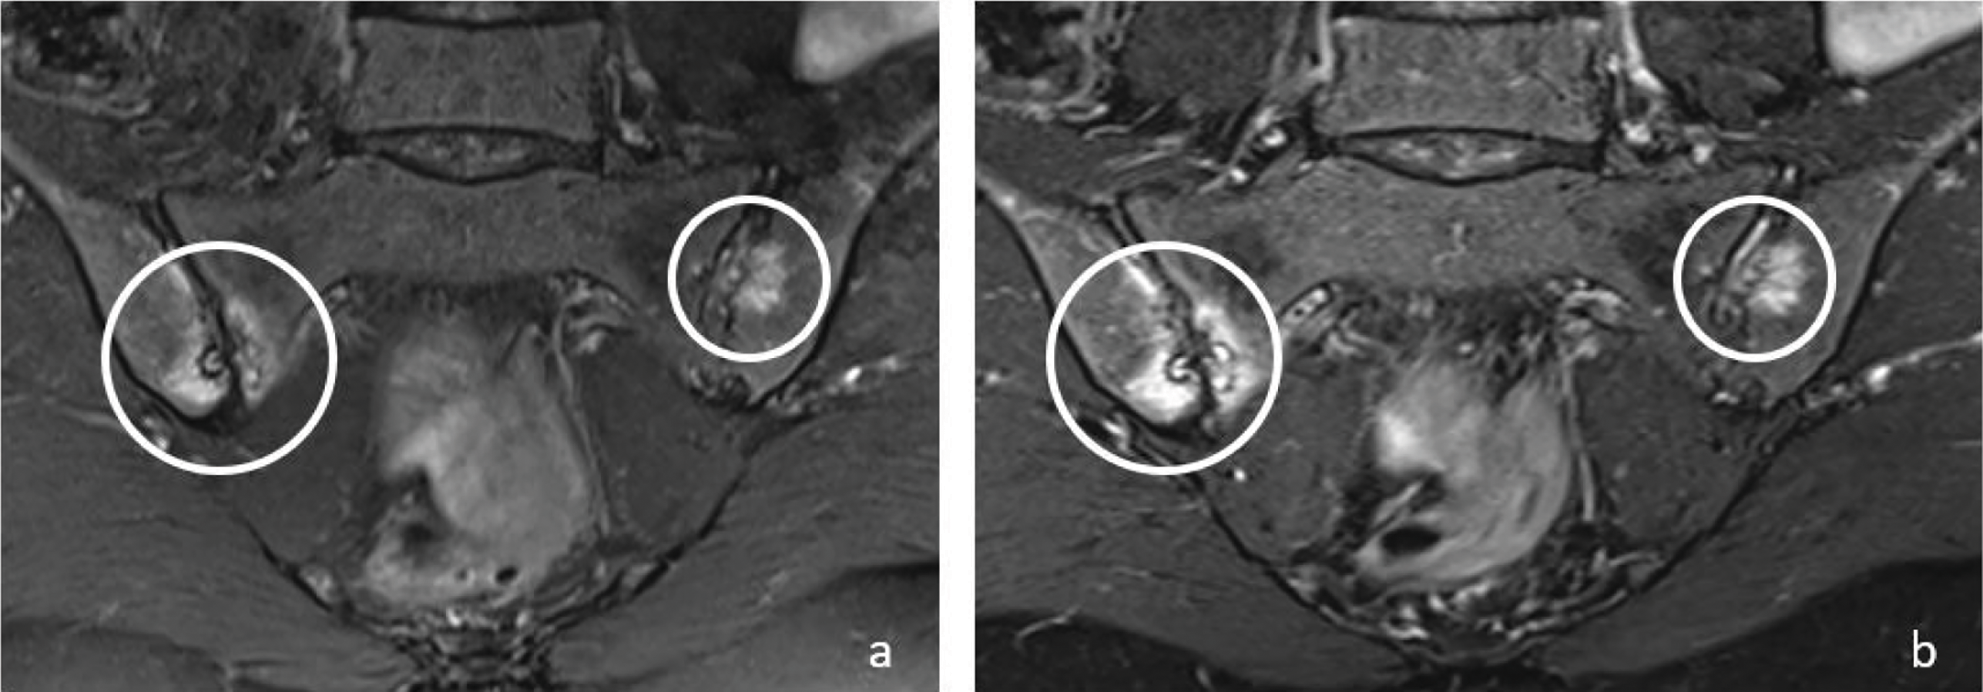

Figure 1

Coronal T2W‑FS (a) and T2W Dixon WO (b) images show bone marrow edema (circles) in both sacroiliac joints on the right sacral and iliac side and on the left iliac side in a 48‑year‑old female patient. Bone marrow edema signals are brighter on T2W Dixon WO images (b).